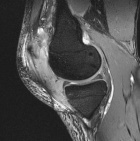

41 year old male c/o left knee mass and swelling. He has a history of T-cell lymphoma diagnosed several years ago. He has been in remission for almost seven years. Six months prior, he began to experience left knee pain and swelling.

Zoom image: Radiological image Radiological image.